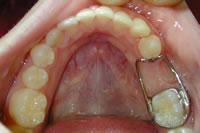

erupting tooth